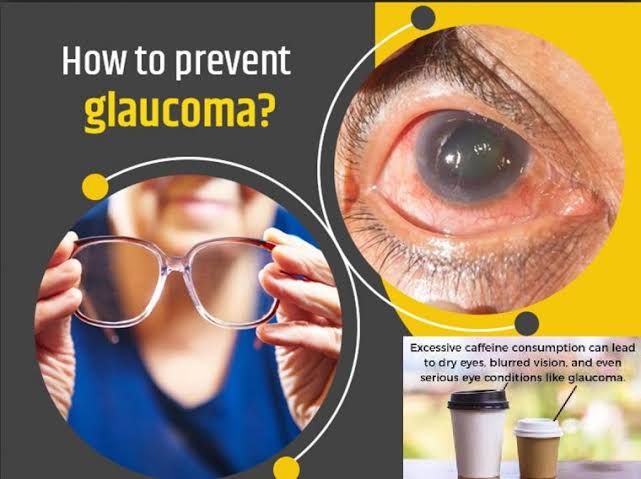

Excessive coffee consumption may lead to blindness The people of Scandinavia suffer from glaucoma, to a...